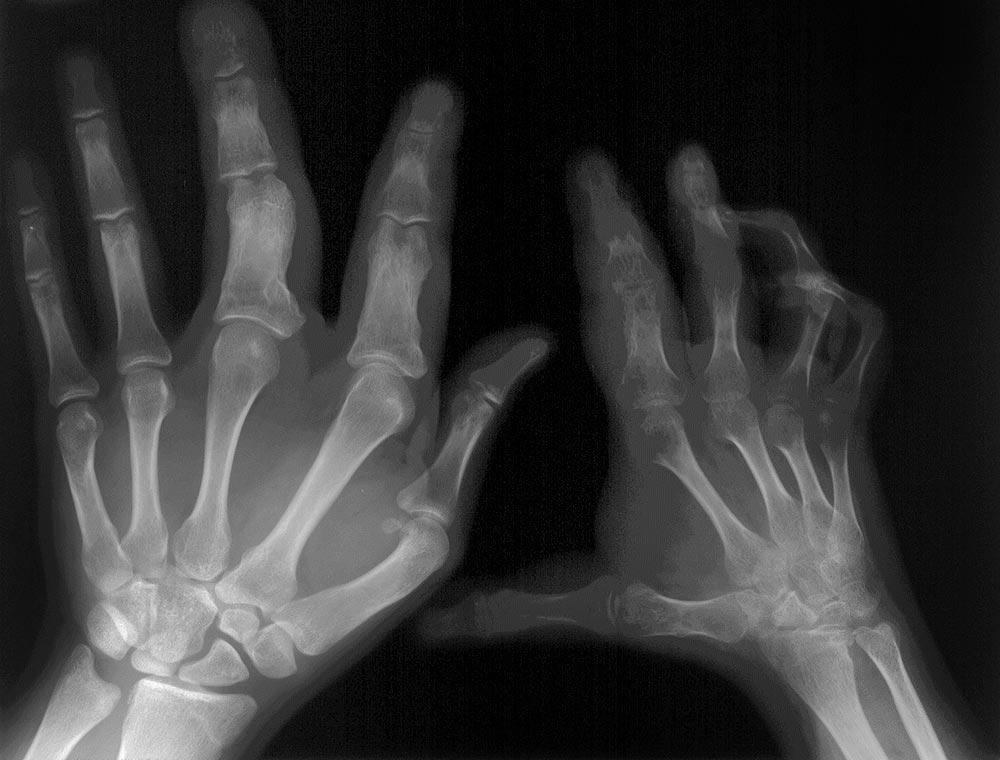

Asymmetry from birth due to circumscribed overgrowth in the extremities (mostly feet) in fibrolipomatous gigantism or overgrowth of one half of the body in hemihyperplasia multiple lipomatosis syndrome (HHML). Subcutaneous, visceral, muscle-infiltrating regional lipomatosis (circumscribed fat hyperplasia), rarely lipomas. During adolescence a major growth phase, often progression of fibrolipomatous overgrowth. In HHML, growth tends to be proportional and not exuberant, whereas in fibrolipomatous overgrowth the clinical picture is characterized by circumscribed, disproportionately progressive gigantism.